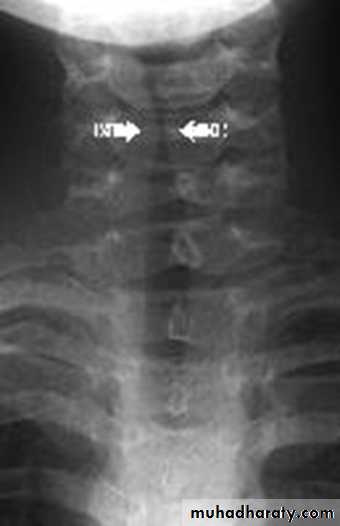

Anteroposterior X-ray of the neck shows subglottic narrowing (steeple sign).